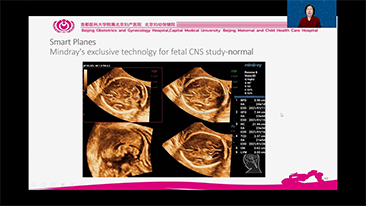

Con la tecnologĂa de la avanzada plataforma ZST+, las soluciones inteligentes completas de la serie Nuewa estĂĄn dise?adas especialmente para mejorar la salud de las mujeres durante el perĂodo previo al embarazo, el embarazo y la recuperaciĂłn en el posparto, con el fin de brindar diagnĂłsticos integrales y eficientes para enfrentar desafĂos clĂnicos cada vez mĂĄs exigentes.